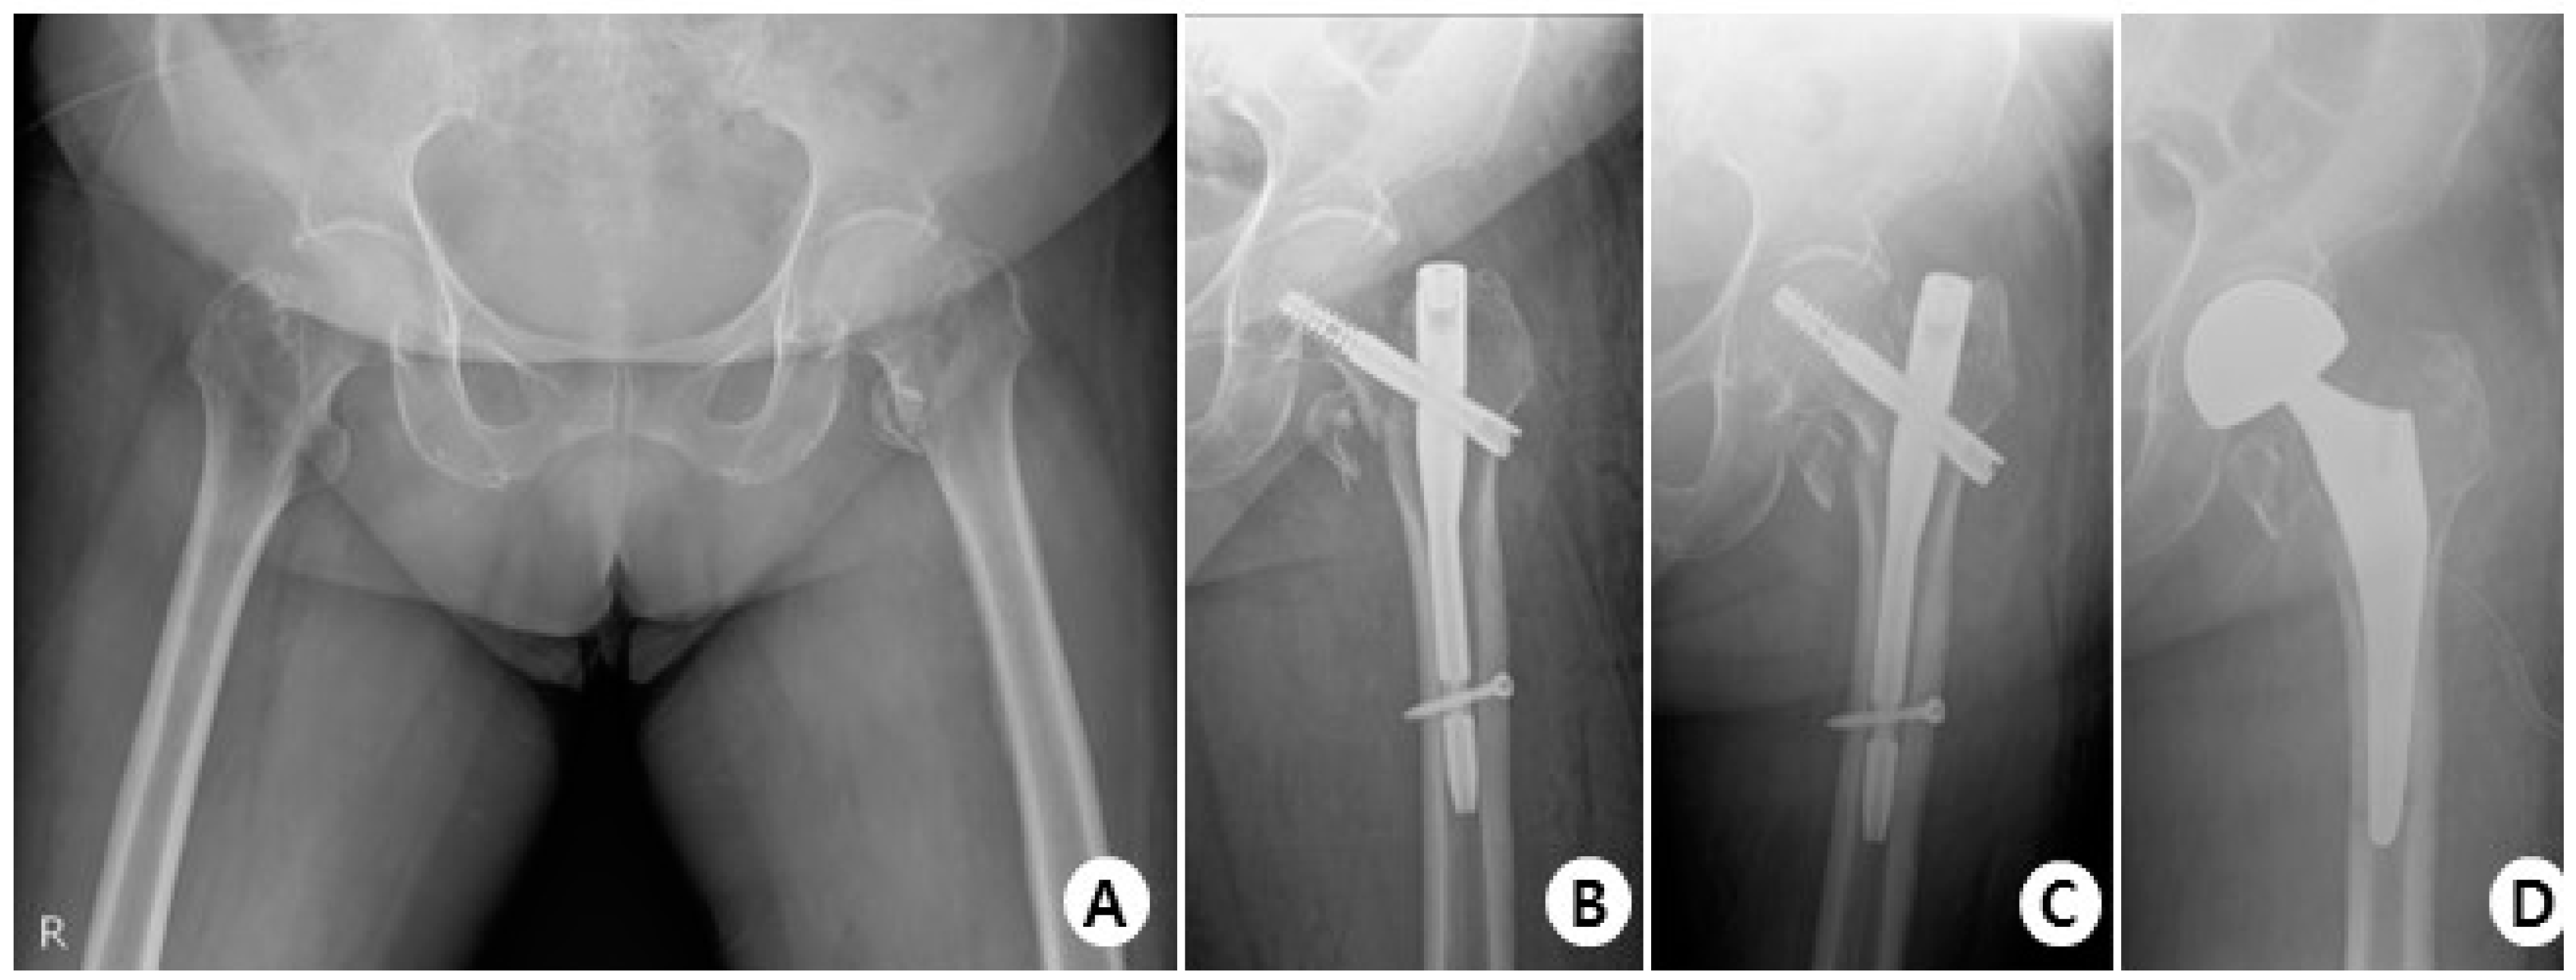

In terms of complications, in the GS group, there were 38 cases with no complications, 3 cases of cut-out (Figure 4), 1 case of non-union, and 1 case of delayed union.

Figure 4.

(A) Total hip AP X-ray of a 76-year-old female diagnosed with an intertrochanteric fracture of the left hip. (B) Immediately post-operation, the fractured segment was reduced in a slight valgus position using the GS hip nail implant. (C) The two months postoperative X-ray shows reduction loss and the progression of varus deformity, with the lag screw experiencing cut-out. (D) X-rays show the revision surgery performed with arthroplasty.

In the Affixus group, there were 34 cases with no complications, 5 cases of cut-out (Figure 5), 1 case of cut through, 4 cases of non-union, 1 case of delayed union, and 1 case of osteolysis.